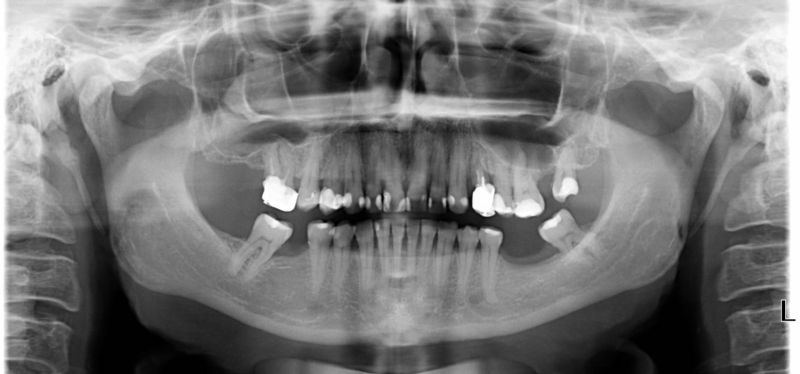

Wykonana praca protetyczna:

- licówki pełnoceramiczne w odcinku przednim zębów górnych

- korony pełnoceramiczne na zęby własne zarówno w łuku dolnym i górnym

- korony na implantach braków zębów